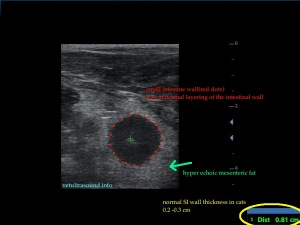

The spleen was increased in size with a diffuse parenchymal hyperechogenicity. A small section of the small intestine was enlarged with loss of its normal wall layers (pic1). The surrounding fat tissue was also hyperechoic. An enlarged regional mesenteric lymphnode was noted with diffuse hypoechogenicity. A Fine Needle Aspiration was performed in order to collect cytology speciments from the spleen and the intestinal lesions. The diagnose was alimentary tract lymphoma.

Image series, through the normal anatomy, to the lesion of the small intestine, in a perpendicular view.